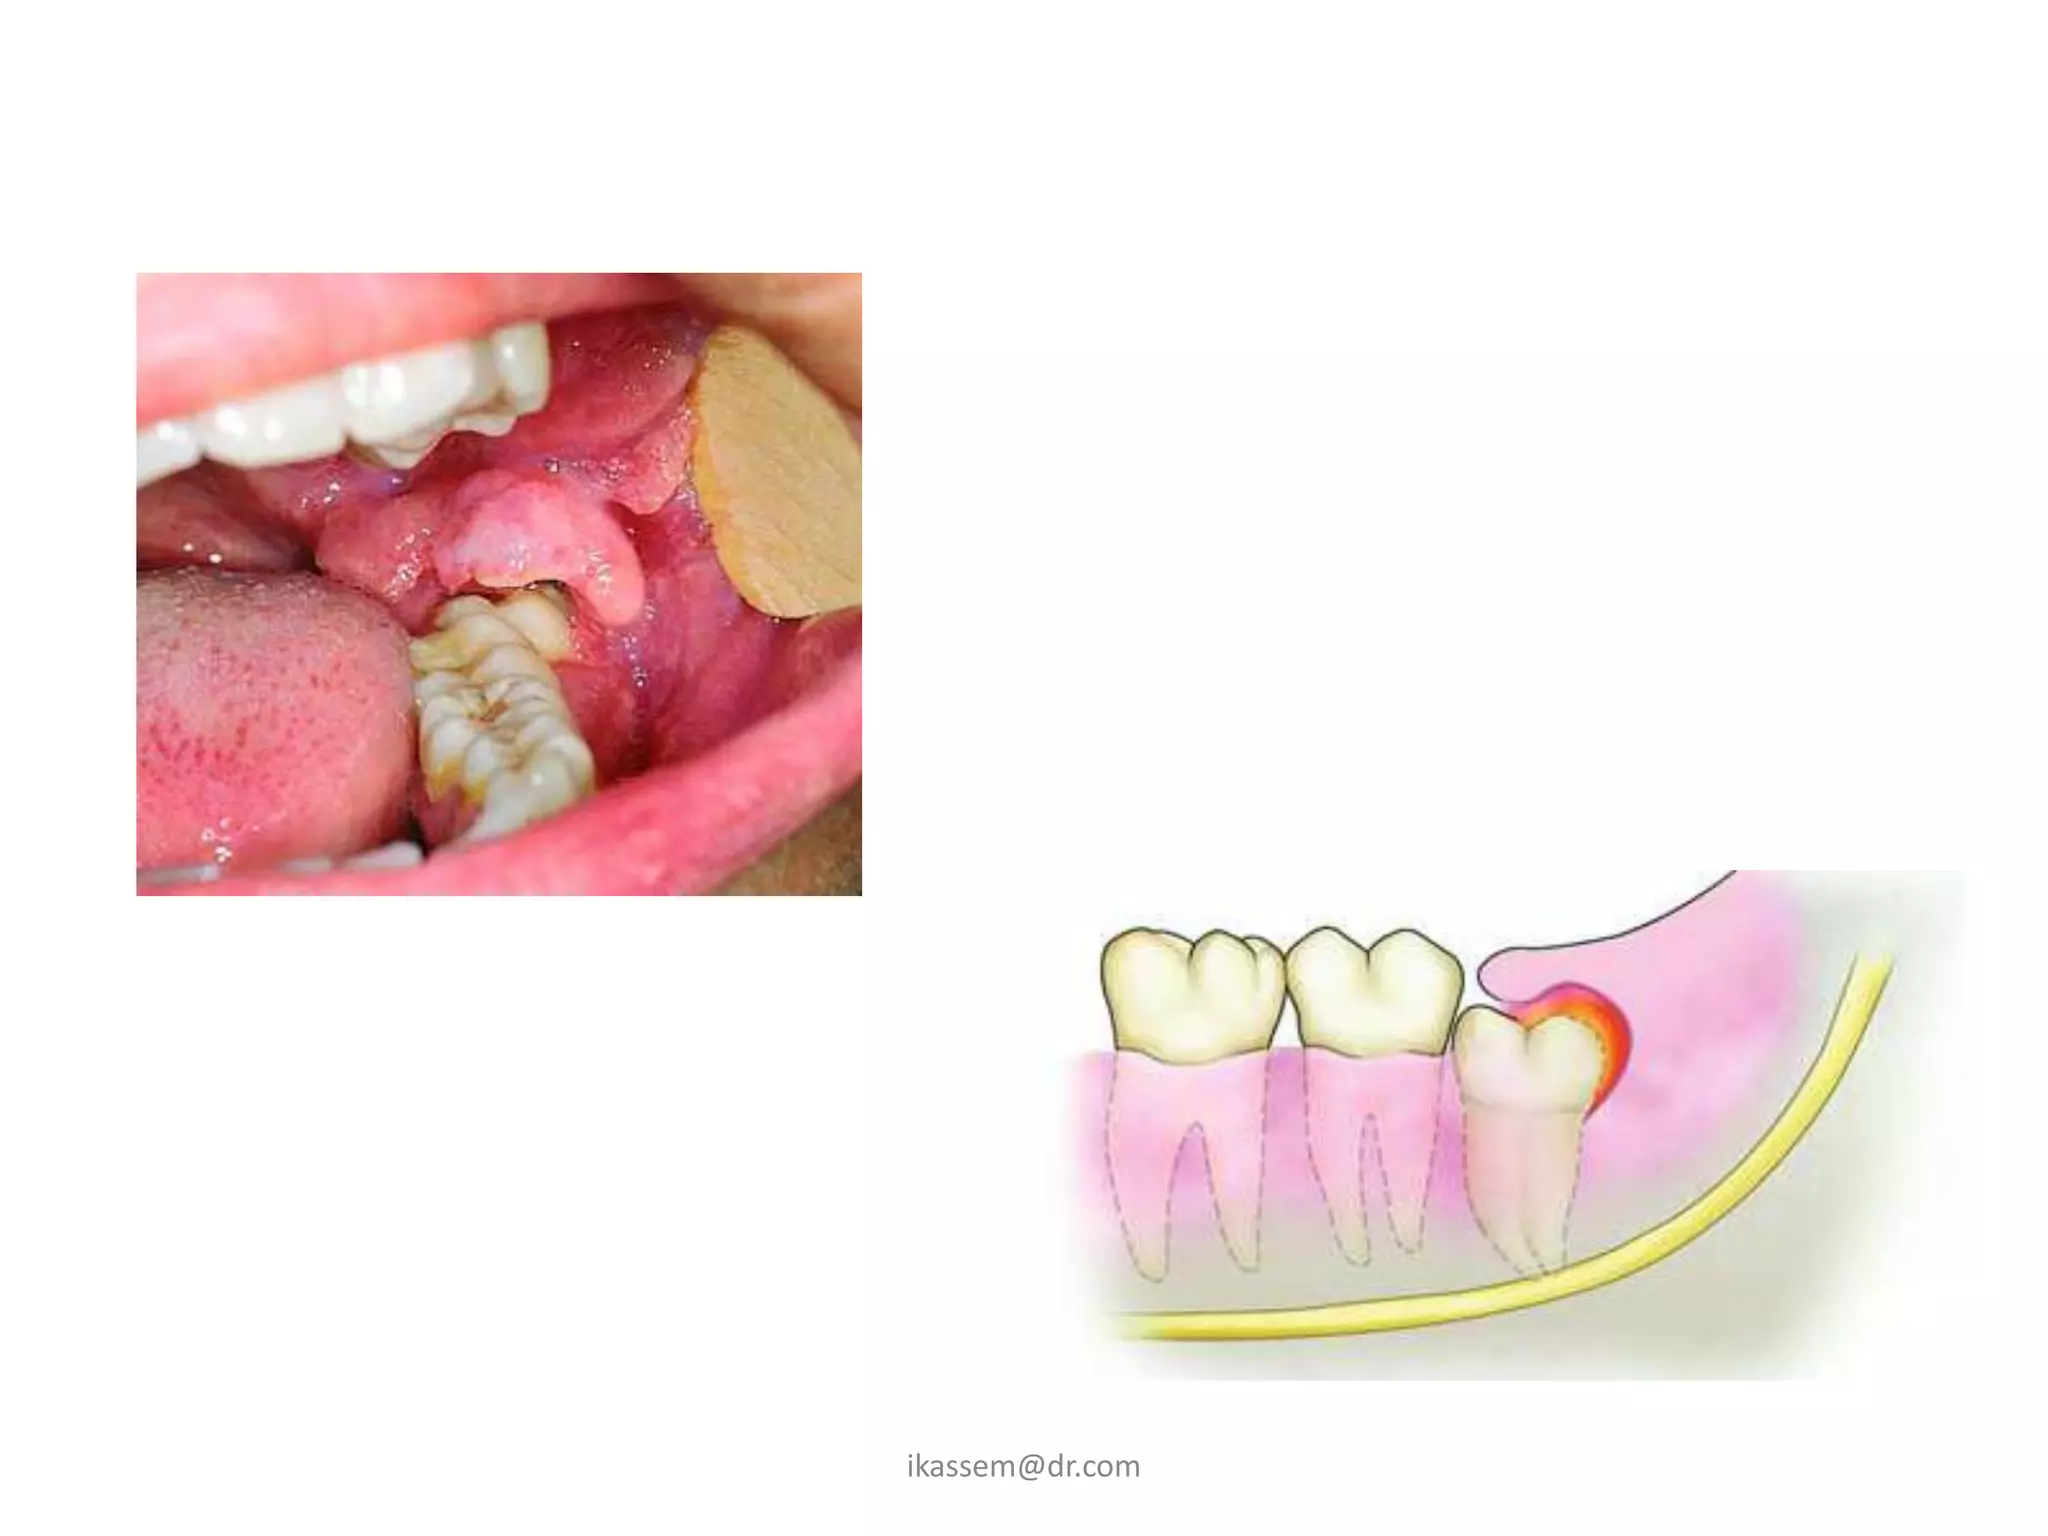

A. Pericoronitis

• when a tooth is partially

impacted with a large

amount of soft tissue over

the axial and occlusal

surfaces, the patient

frequently has one or more

episodes of pericronitis.

Definition of pericoronitis

• is an infection of the soft

tissue around the crown of

partially impacted tooth and is

caused by the normal oral

flora.